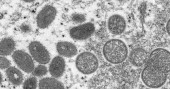

Monkeypox is a virus that originates in wild animals like rodents and primates, and occasionally jumps to people. Most human cases have been in central and west Africa, where the disease is endemic.

The illness was first identified by scientists in 1958 when there were two outbreaks of a “pox-like” disease in research monkeys — thus the name monkeypox. The first known human infection was in 1970, in a 9-year-old boy in a remote part of Congo.

Monkeypox belongs to the same virus family as smallpox but causes milder symptoms.

Most patients only experience fever, body aches, chills and fatigue. People with more serious illness may develop a rash and lesions on the face and hands that can spread to other parts of the body.